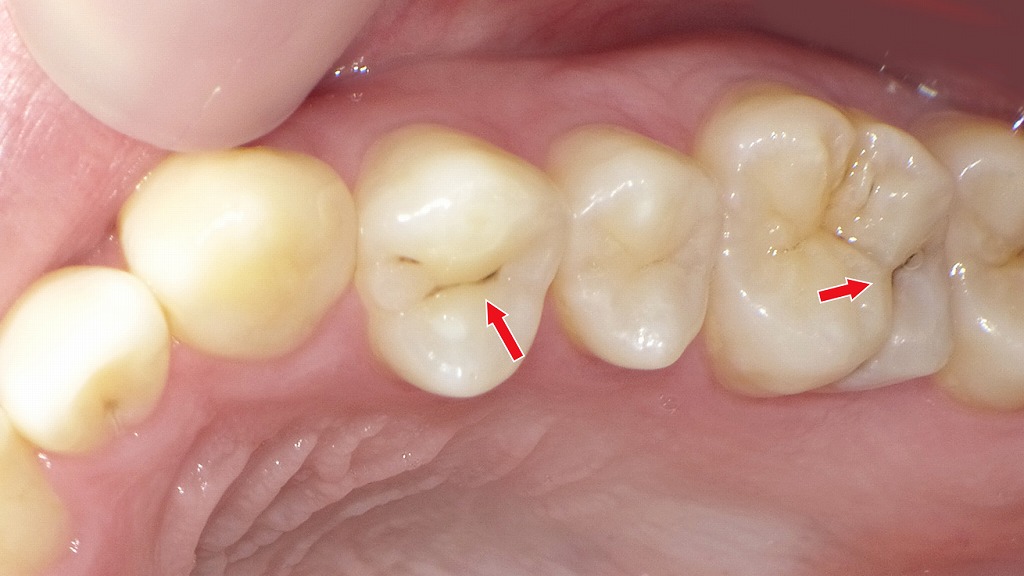

初期虫歯(C1)

初期虫歯(C1)は、虫歯がエナメル質の内部まで進行し始めた段階を指します。まだ穴は大きく開いておらず、痛みやしみる症状が出ないため、自覚しにくいのが特徴です。見た目としては、黒い点や小さな溝の変色として確認されることが多く、歯科医師による診断が重要になります。

C2の場合:必要最小限の虫歯除去+CR充填

C2は虫歯がエナメル質を越えて象牙質まで進行した段階で、痛みやしみる症状が出始めることがあります。象牙質は軟らかく、C1より進行が早いため、自然な再石灰化での改善は困難です。

そのため、C2では虫歯に侵された部分のみをできる限り小さく削り、その後コンポジットレジン(CR)で修復する治療が基本となります。